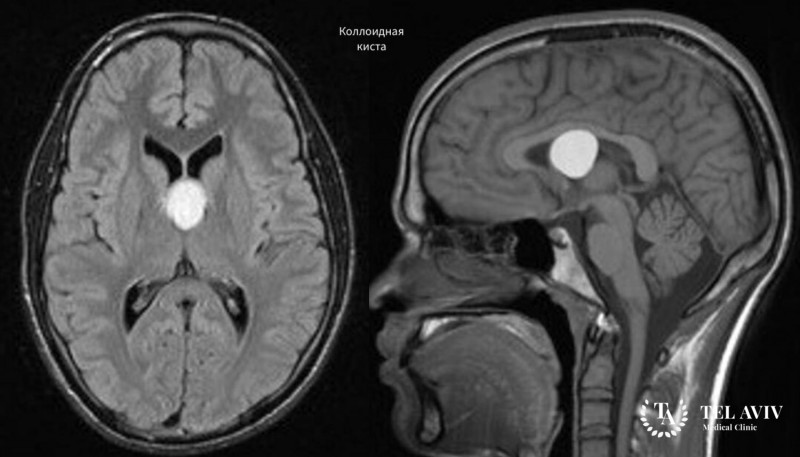

Коллоидная киста головного мозга – это опухолевое заболевание, которое локализуется в полости III желудочка головного мозга. Изначально новообразование имеет незначительные размеры (до 5 миллиметров), но под воздействием определенных факторов киста начинает увеличиваться в размерах. До конца не изучено, что является триггером для ее роста, однако некоторые исследования говорят о том, что росту новообразования могут способствовать недосыпания, переутомляемость, сильные стрессы, курение и злоупотребление алкоголем.

Постановка диагноза

Врач проводит опрос и осмотр пациента, и в случае возникновения подозрений на опухолевое заболевания мозга направляет пациента на компьютерную томографию головного мозга, ПЭТ-МРТ и офтальмологическое обследование. В большинстве случаев для постановки правильного диагноза такой диагностики вполне достаточно.